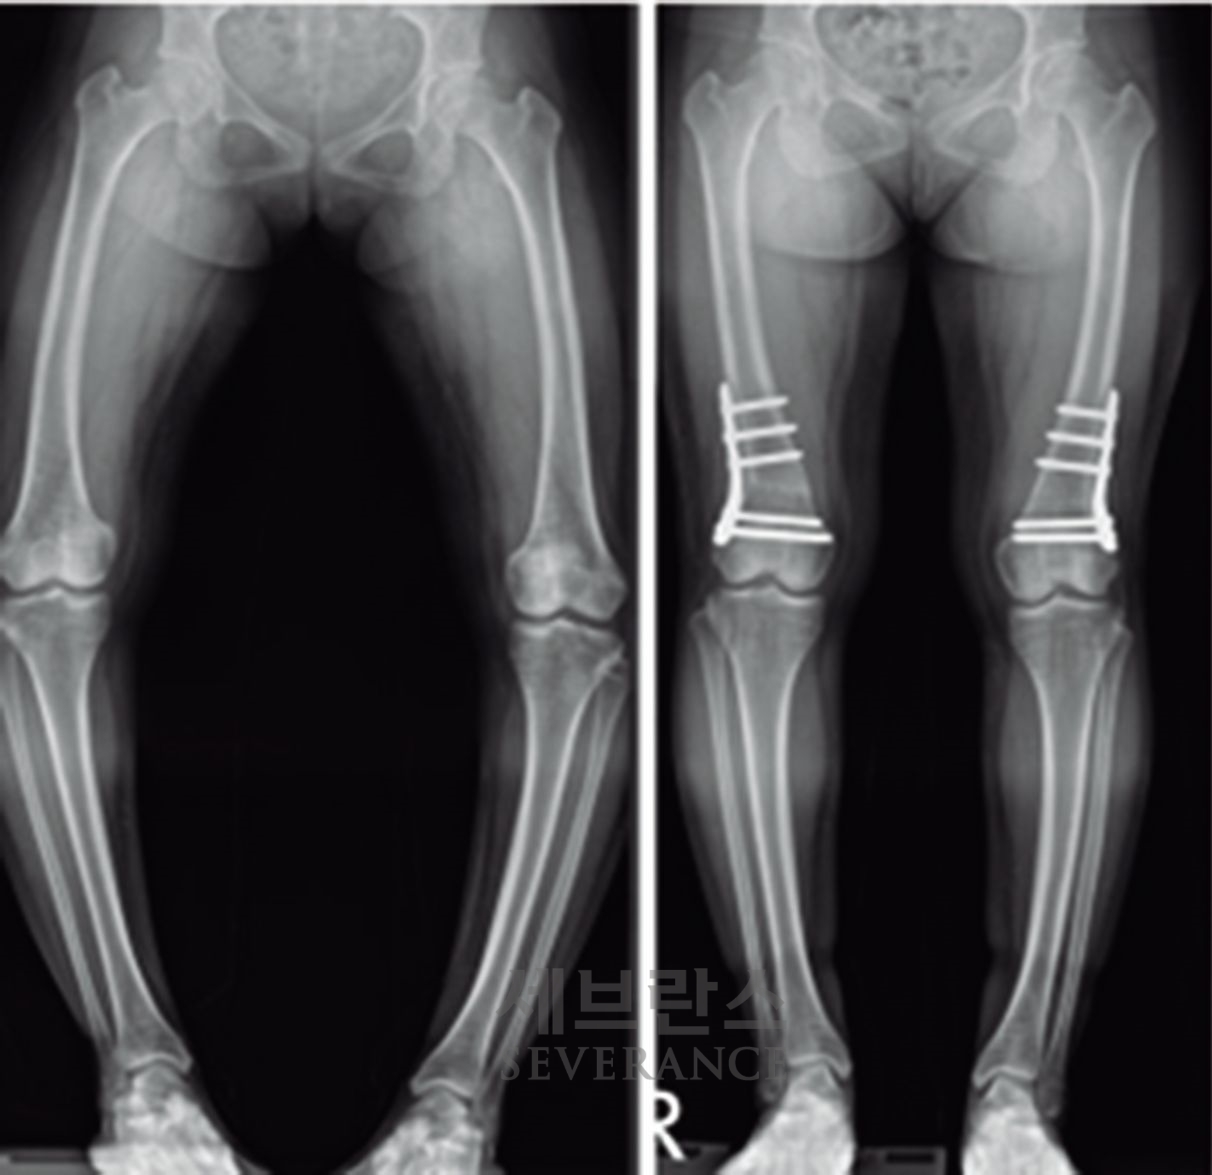

특발성 대사성 질환으로 인한 외반슬(X다리)에서 성장조절술을 시행한 환아성장판

성장판이 열려 있는 아이에게 많이 사용되는 성장조절술은 한쪽 성장판의 성장을 일시적으로 억제해 시간이 지나면서 다리 길이나 각도가 서서히 교정되도록 하는 방법입니다. 일반적으로 심하지 않은 O다리나 X다리, 경미한 다리 길이 차이에 적용합니다. 흉터가 작고 회복이 빠르지만, 효과가 나타나기까지 시간이 필요하고 성장이 끝난 아이에게는 사용할 수 없습니다. 또 교정이 완료된 후에도 성장 과정에서 일부 각도가 다시 돌아오는 ‘성장 반동’ 현상이 나타날 수 있습니다. 따라서 성장판이 완전히 닫힐 때까지 정기적으로 추적 관찰을 받아야 합니다.